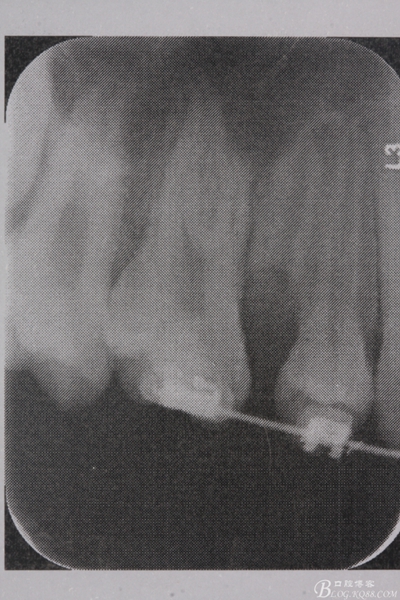

圖4. 加拍局部根尖片,15牙根顯露無疑,遂考慮拔除15,才能關(guān)閉16與14之間的間隙。